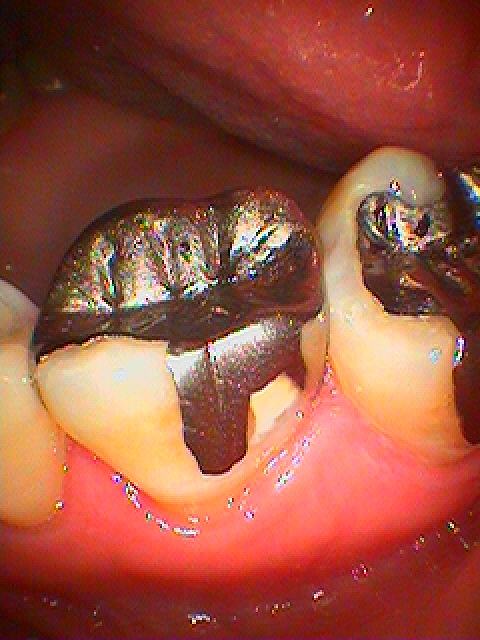

お知らせ|広島市安佐南区の歯科医院 > お知らせ トップ お知らせ・ブログ お知らせ スタッフブログ お知らせ お知らせ 2021/08/18 ジルコニアクラウンの作成 連冠にてジルコニアクラウンを作成していきます お知らせ 2021/08/18 左下の奥の歯茎がいつも痛くなる 近くの歯医者では親知らずが原因だと言われた 親不知を抜いてもらえる歯医者を探してきた お知らせ 2021/08/18 右上6番の銀歯を外していきます 銀歯の下は大きく虫歯になっていることがあります あなたの銀歯は大丈夫? 40代男性 お知らせ 2021/08/17 左上のインプラント埋入2本 50代男性 奥歯でも噛めなくて嚙めるようにしたくてこころ歯科へ来院 お知らせ 2021/08/17 右下親知らずの水平埋伏の難抜歯 30代男性 近くの歯医者では抜けなくて抜いてもらえるところを探してきた お知らせ 2021/08/17 右下6番の虫歯治療 30代女性 白いセラミック治療 お知らせ 2021/08/11 右上の6,7番をセラミックにて修復してい置きます 30代女性 お知らせ 2021/08/11 左上の最後臼歯部のインプラント埋入 抜歯して3か月になります 30代女性 お知らせ 2021/08/11 右下水平埋伏の難抜歯 30代後半男性 近くの歯医者ではずっとここでは抜けないといわれ続けてきた お知らせ 2021/08/10 こころ歯科クリニックでの審美クラウンの作成 ジルコニアクラウンを用いた前歯部の審美治療 << 1 2 3 4 5 … 197 198 199 200 201 … 485 486 487 488 489 >> Web診療予約 初めての方へ 選ばれ続ける理由 院内設備について 歯が痛いしみる一般歯科 歯がぐらぐらする歯周病 健康な歯を保ちたい予防歯科 子供の虫歯予防をしたい小児歯科 銀歯をセラミックに審美歯科 白い歯を目指しませんか?ホワイトニング 矯正専門医がいるので安心矯正歯科 抜けた歯を補いたいインプラント・入れ歯 医院案内 スタッフ紹介 メリィハウス歯科クリニックオフィシャルホームページ ラベンダー歯科クリニックオフィシャルホームページ お知らせ・ブログ ホーム 診療科目 一般歯科 歯周病治療 予防治療 小児歯科 審美治療 ホワイトニング 矯正歯科 入れ歯・インプラント マウスピース矯正 初めての方へ 院長・スタッフ 設備紹介 医院案内・アクセス メニューを閉じる